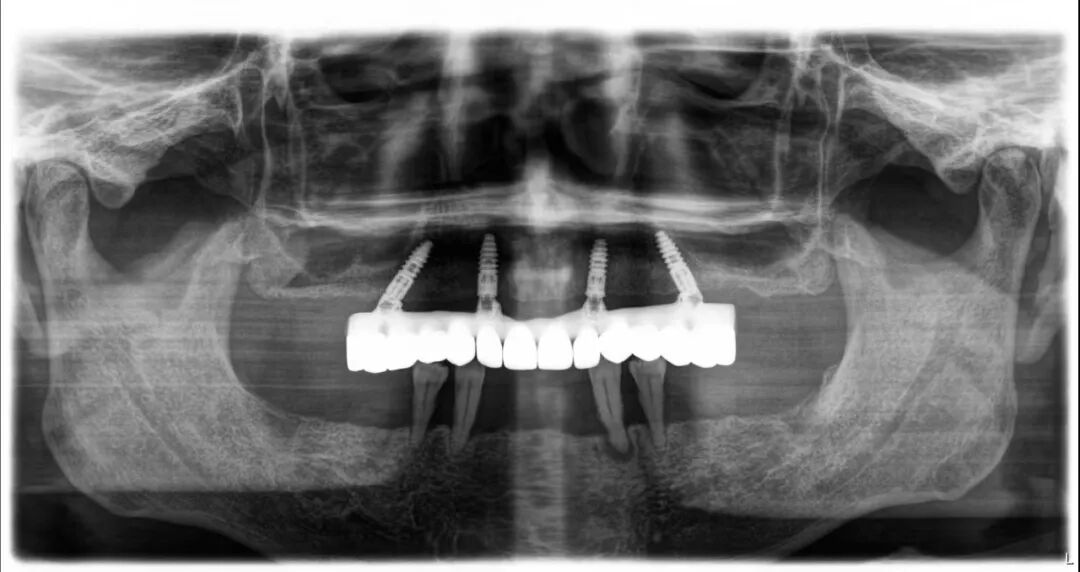

经过专业、严谨的评估,李志峰院长为高叔叔量身定制了专属种植方案:上颌进行all-on-4手术,即刻负重;下颌佩戴临时活动义齿两颗,待上颌恢复后再进行种植。

手术中,李志峰院长凭借专业、娴熟的技术,结合国际领先的数字化种植体系,以微米级的精准定位,实现了微创、安全、无痛的种植。整个过程创口小、时间短,大大减轻了患者的身体负担。

术后仅2小时,高叔叔便成功戴牙,即刻恢复了咀嚼功能。他说:“以前特别喜欢啃猪蹄,自从牙坏了就很少吃了,这次做完手术要把这几年吃不了的东西都吃个遍。”